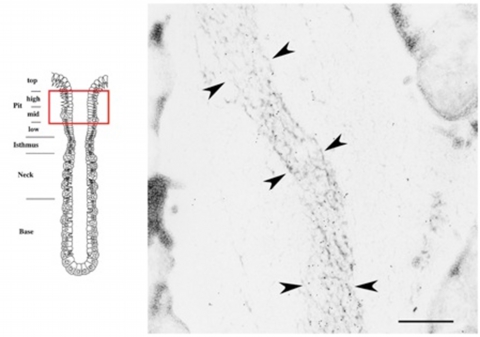

胃底腺底部の主細胞(CC)から分泌された漿液成分(矢印)

漿液成分は滴状形態を保持して頚部腺腔内(L)を上昇